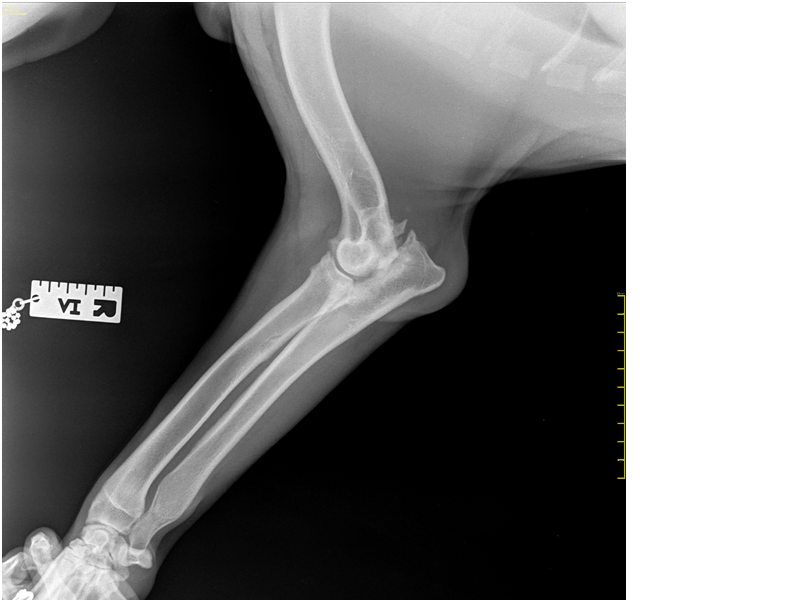

Рентген Задней Лапы Кошки: Нормы и Диагностика